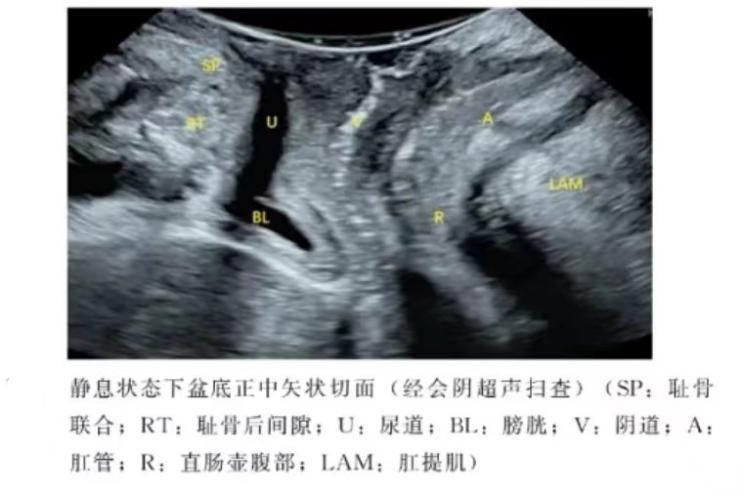

盆底超声是将探头放于会阴部或阴道内,通过指导患者正确的完成缩肛和 Valsalva 动作,动态观察盆腔脏器的位置变化,从而判断盆腔脏器的脱垂情况及盆底肌肉的完整性。

盆底三维成像技术还可以获得完整的肛提肌裂孔的立体声像图,准确测量裂孔大小,直观地观察肛提肌及韧带走形及损伤程度。盆底超声被广泛应用于盆底功能障碍性疾病的诊断和治疗后疗效的评估。